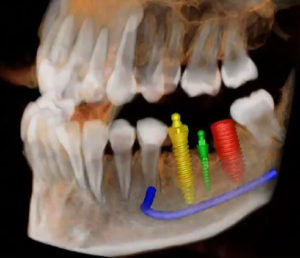

18% of general practitioners in the US are placing implants. Accuracy is significantly increased when armed with CBCT, eliminating contingency treatment plans and surprises during implant surgery. Prior to having these systems, many practitioners were handling implant placement freehand. Medically, you are on much firmer ground when you have cone beam in place. It’s akin to having GPS technology: you know the size, what brand, and where to place the implant in the patient’s mouth.

The CBCT measures an exact one-to-one ratio with no superimposed structures or magnification. This way, you can precisely measure in between implants to ensure you have the proper room from one implant to another, and you can assess the bone quality and quantity. Specialists can place a single implant in roughly 15 minutes if they are well prepared.

These days, patients are more aware of this technology, and it’s not uncommon for them to ask whether you will be using CBCT as a surgical guide for their implant procedure. Prior to the procedure, can have them sign off on pictures, so they have a full understanding of the treatment plan, and so that you are better covered legally.